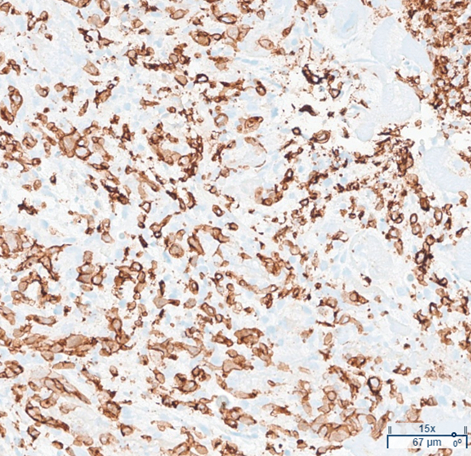

Abstract Body (Do not enter title and authors here): Case: A 64-year-old male with stage IV squamous cell carcinoma on durvalumab (last dose 2 months prior) presented with acute dyspnea on exertion. Vitals were notable for heart rate of 128 beats per minute and oxygen saturation of 92% on 4 liters of nasal cannula. EKG showed ST elevation in V1-2 and aVR, with reciprocal ST depressions in II, III, and aVF. Labs revealed troponin >10,000 ng/L and BNP 14,492 pg/mL. Computed tomography angiography (CTA) ruled out pulmonary embolism. Transthoracic echocardiogram (TTE) showed left ventricular ejection fraction (EF) 48% with hypokinesis of the left ventricular septum. Emergent coronary angiography demonstrated non-obstructive coronary artery disease. Cardiac MRI revealed mid-myocardial late gadolinium enhancement, and endomyocardial biopsy confirmed CD8+ T-cell infiltration consistent with ICI-induced myocarditis. His hospital course was complicated by an episode of sustained monomorphic ventricular tachycardia, managed with amiodarone, followed by placement of a subcutaneous implantable cardioverter-defibrillator. Treatment with high-dose corticosteroid therapy followed by Abatacept for ICI-induced myocarditis led to resolution of symptoms and improvement in cardiac biomarkers, allowing for the patient to be safely discharged.